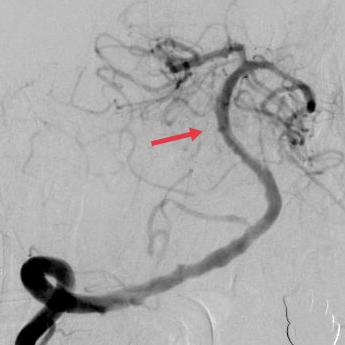

12:26分:急性脑梗死、基底动脉闭塞诊断明确后,卒中介入小组急诊完成全脑血管造影术+右侧椎动脉取栓术+基底动脉球囊扩张术+基底动脉支架植入术。全程进展顺利,入院到基底动脉再通时间为73分钟。

脑血管造影可见基底动脉闭塞

右侧椎动脉取栓后可见基底动脉“线样征”。

行基底动脉球囊扩张术+基底动脉支架植入术后,基底动脉开通。